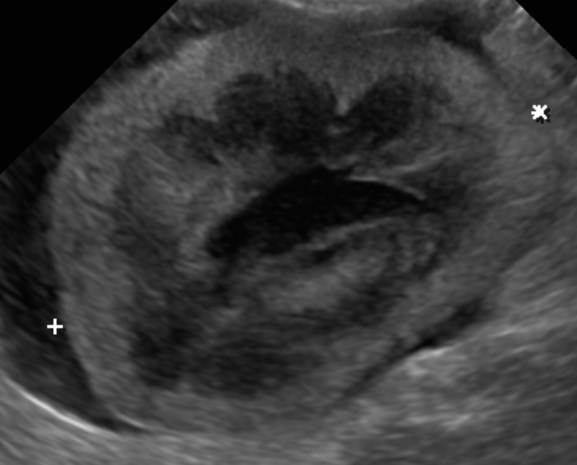

影像結果

超音波顯示腎臟型態異常